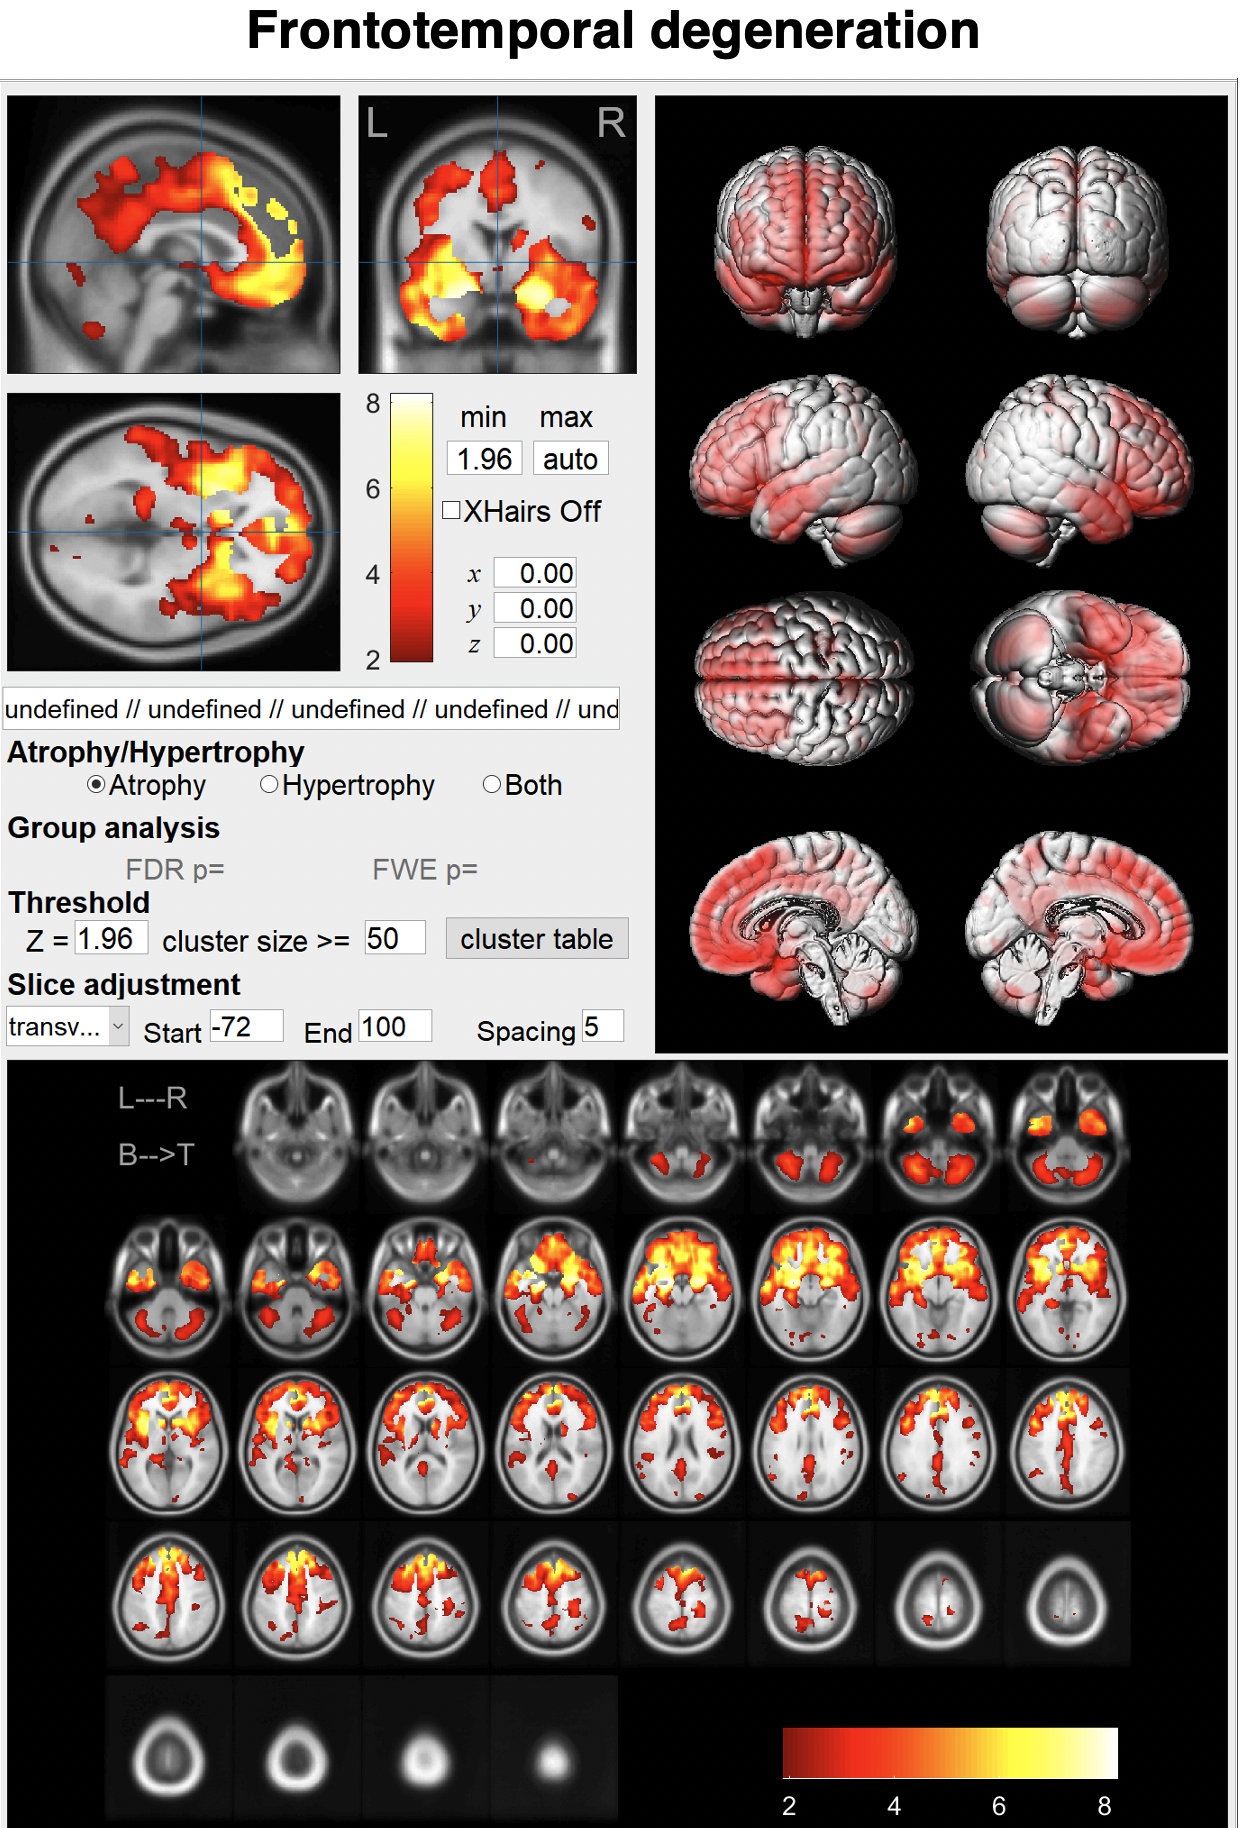

○脳の形態と機能 画像医学の進歩,

○脳の形態と機能 画像医学の進歩, BAAD HP ja,

BAAD HP ja, 研究 | 東京科学大学 脳神経病態学分野(脳神経内科),

研究 | 東京科学大学 脳神経病態学分野(脳神経内科), あなたの脳,

あなたの脳, 3D-SSP解析とZ-Graphについて | 日本メジフィジックス株式会社,「脳の形態と機能 画像医学の進歩」福田寛定価: ¥ 11,000#福田寛 #本 #BOOK #健康 #医学#書籍 #古本 #趣味 #安い#勉強#テキスト★補足★・簡易的な確認にて書き込みやマーカーはございませんでしたが、見落としている場合もあるかと思いますので神経質の方は御遠慮ください。骨粗鬆症を原因とした脊椎圧迫骨折の病態理解と運動療法 希少本 赤羽根良和 初版。・保管品のため多少の細かい傷やホコリ等の汚れはあると思いますので、神経質の方は御遠慮ください。クエスチョンバンク 臨床検査 2025。・梱包方法に関しての要望は受け付けません。イメージ健康体操 経絡体操 増永静人。写真の状態でお手元に届くよう、極力プチプチやビニール 等を使用したり工夫は致しますが、細かく要望がある方は御遠慮ください。【裁断済み】白内障手術ロジカルテクニック。・返品やクレームに関しては受け付けておりません。【裁断済み】DSM-5 精神疾患の診断・統計マニュアル。

3D-SSP解析とZ-Graphについて | 日本メジフィジックス株式会社,「脳の形態と機能 画像医学の進歩」福田寛定価: ¥ 11,000#福田寛 #本 #BOOK #健康 #医学#書籍 #古本 #趣味 #安い#勉強#テキスト★補足★・簡易的な確認にて書き込みやマーカーはございませんでしたが、見落としている場合もあるかと思いますので神経質の方は御遠慮ください。骨粗鬆症を原因とした脊椎圧迫骨折の病態理解と運動療法 希少本 赤羽根良和 初版。・保管品のため多少の細かい傷やホコリ等の汚れはあると思いますので、神経質の方は御遠慮ください。クエスチョンバンク 臨床検査 2025。・梱包方法に関しての要望は受け付けません。イメージ健康体操 経絡体操 増永静人。写真の状態でお手元に届くよう、極力プチプチやビニール 等を使用したり工夫は致しますが、細かく要望がある方は御遠慮ください。【裁断済み】白内障手術ロジカルテクニック。・返品やクレームに関しては受け付けておりません。【裁断済み】DSM-5 精神疾患の診断・統計マニュアル。